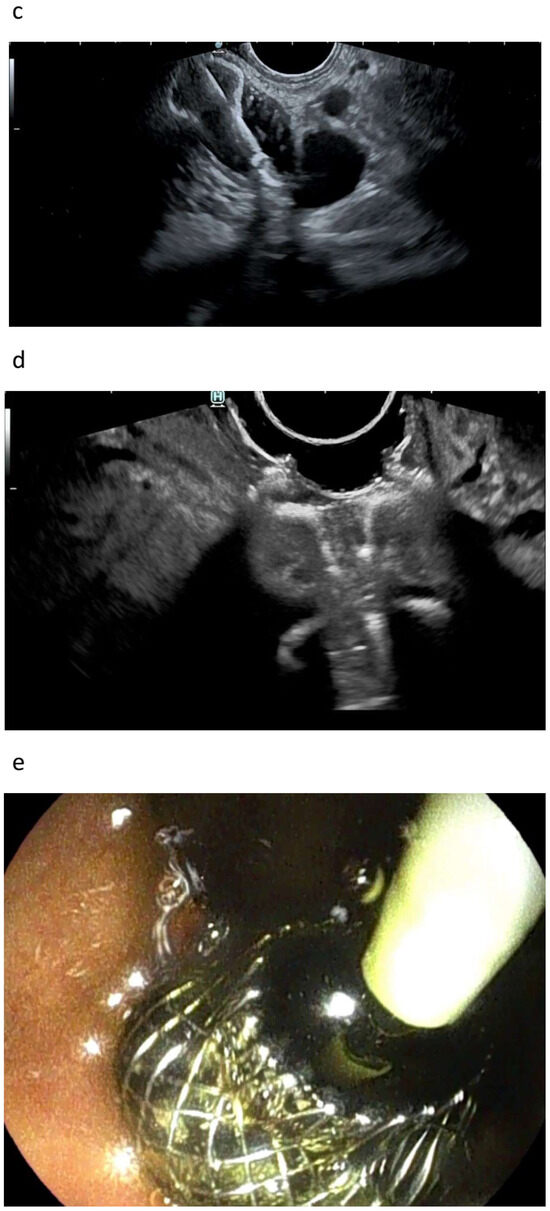

3.1.1. EUS-BD of the Bile Duct

3.1.2. EUS-GBD

3.2. Arguments against EUS-Guided Drainage

7. Do We Need Cystotomes?

8. Do We Need Bougies?

10. Plastic or Metal Stents?